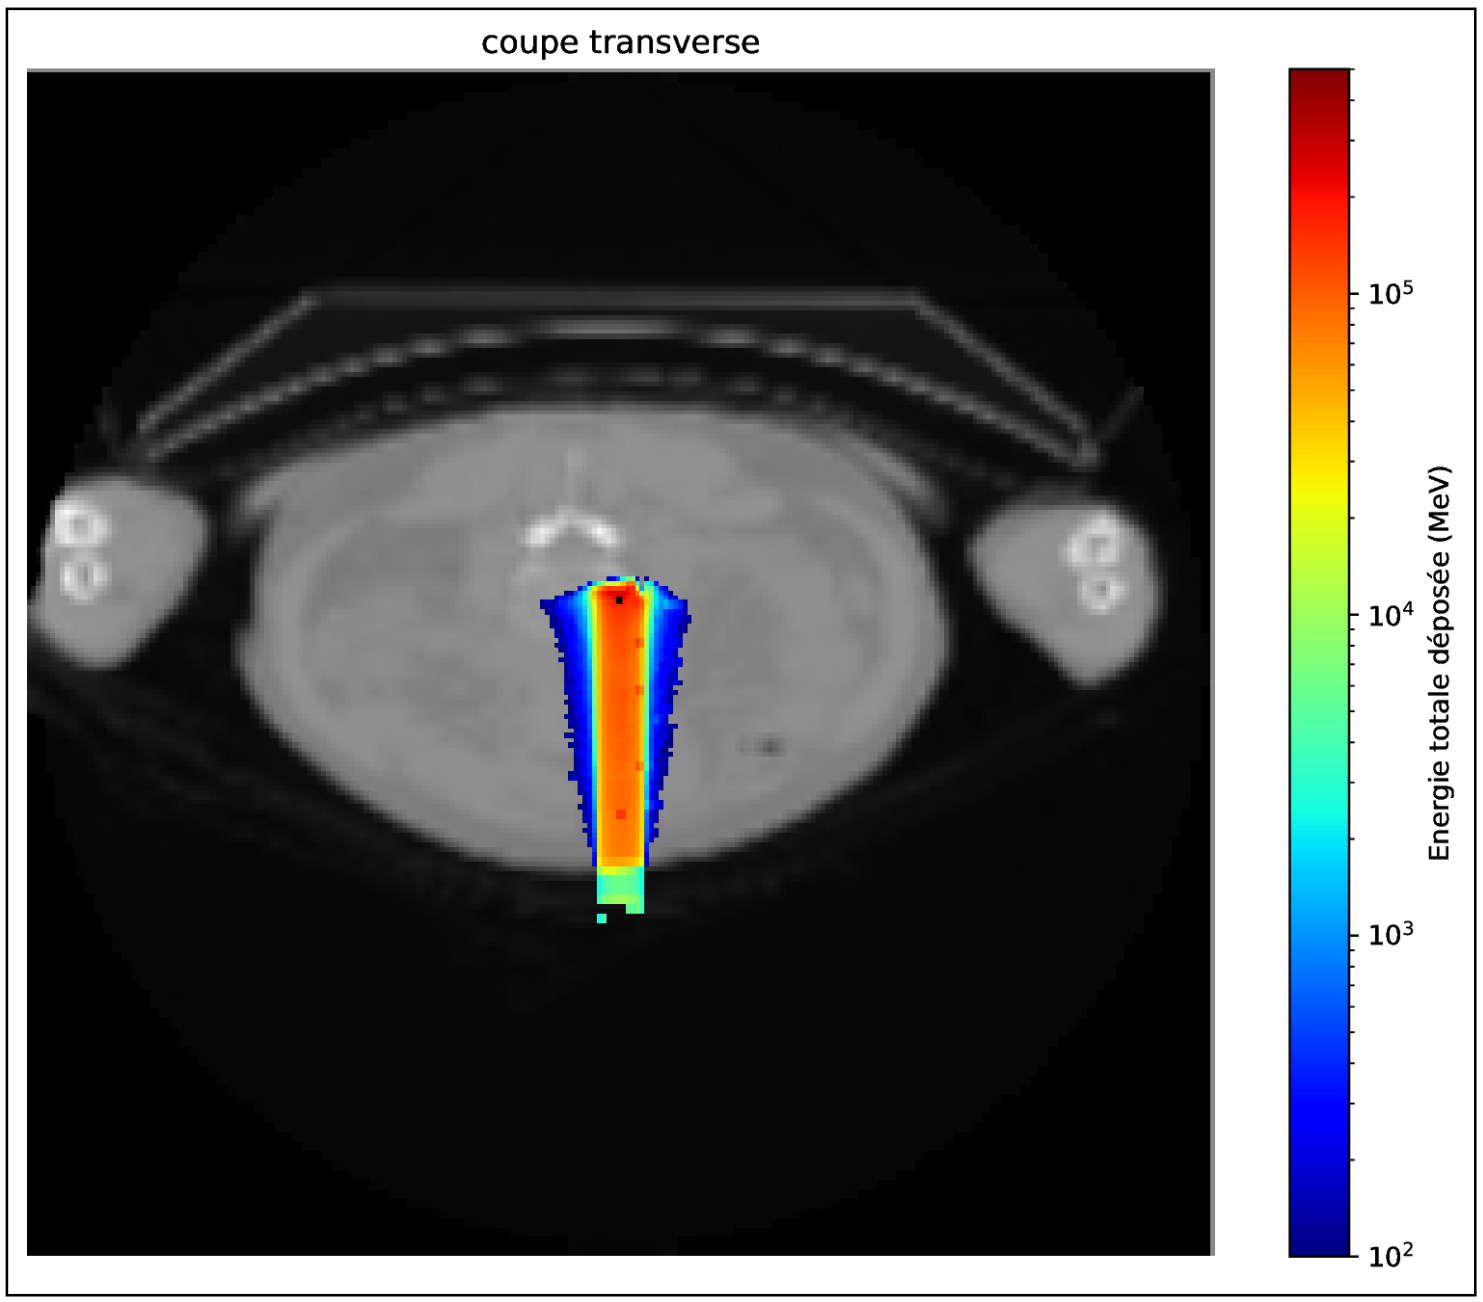

Figure 1. En haut : énergie totale déposée sur un scan CT pour un faisceau proton (107 – 130 MeV) incident placé sur l'axe antéro-postérieur et un carré noir pour pour situer le voxel d'intérêt (VOI). Milieu et bas : comparaison entre la simulation analogue (rouge) et vpgTLE (bleu) des rendements PG selon leur énergie (gauche) et leur temps (droite) pour le VOI.